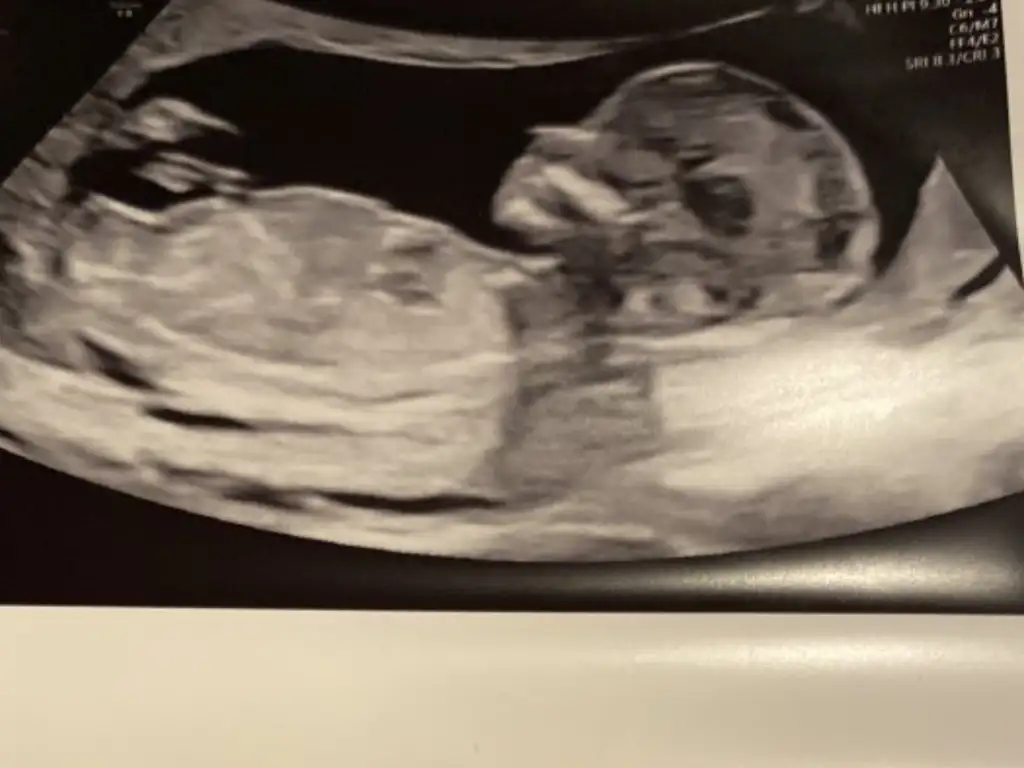

Erkek sankiMerhaba arkadaşlar benim için de tahmin yapabilir misiniz rica etsem 13+4 doktor bir tahminde bulundu ama emin olamadı. Sizin yorumlar nelerdir acaba

Daha önce de sormuştum ikra meyra hanıma ona erkek görünüyor dedi ama doktor kıza benziyor dedi emin olamadı ama burda kime sorduysam erkek gibi dedi. 2 kızım var bu 3. Bebeğim gönül olmayanı istiyor ama herseyin başı sağlık sağlıklı olsun da ne olursa olsun. Tabi merak işte. İnsan merakına yenik düşüyor. Çok teşekkür ederim yorum içinErkek sanki

İki hafta sonra gidecem doktora ozman netleşir.Daha önce de sormuştum ikra meyra hanıma ona erkek görünüyor dedi ama doktor kıza benziyor dedi emin olamadı ama burda kime sorduysam erkek gibi dedi. 2 kızım var bu 3. Bebeğim gönül olmayanı istiyor ama herseyin başı sağlık sağlıklı olsun da ne olursa olsun. Tabi merak işte. İnsan merakına yenik düşüyor. Çok teşekkür ederim yorum için